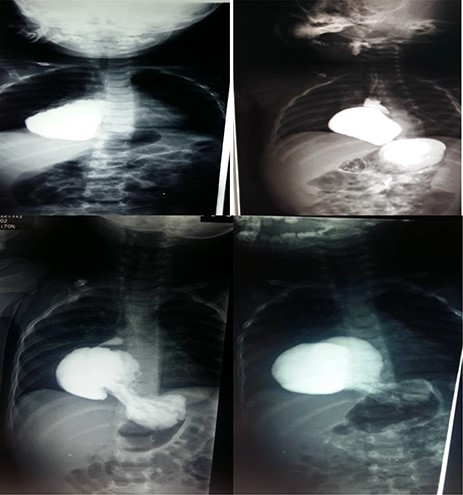

Upper left photo is of case two that shows a barium swallow with 5.5 cm hiatus hernia. The upper right photo is of case 4 that shows a barium swallow with 8 cm hiatus hernia. Lower 2 photos are of case 3 that show barium swallow with a 6 cm hiatus hernia.

An 8-month-old boy was admitted with a 20-day history of black, loose diarrhoea (5–6 occurrences in total) with no frank blood in the stool. He had low fever. Lab tests were normal with positive stool occult blood test. Following symptomatic treatment for 2 weeks, an endoscopy was conducted which showed a displacement of the LES with mild lower ulcerative oesophagitis and was confirmed later on with a plain X-ray and a barium meal to be an 8 cm HH (see Fig. 3). The HH was repaired with Nissen open surgery.

An 18-month-old boy was admitted to the Children Hospital with a 3-week history of progressive pallor and 1 day history of melena after which his parents brought him to a private clinic when a chest X-ray showed that he had HH with the stomach being in the chest cavity with an enlarged left pulmonary hilum and right mediastinum displacements (see Fig. 3). CBC showed that he was also severely anaemic (Hb: 6 g/dl). He reported no other symptoms and had not been prescribed any previous medications. An endoscopy was performed which showed an abnormal location of the stomach in the thoracic cavity. The barium meal was obtained which confirmed the HH. In open surgery from the abdomen, the stomach and the oesophageal hiatus were found to be herniated into the thoracic cavity. They were repaired with Nissen surgery.

A 38-month-old girl was admitted with 2-week history of epigastric pain and 10-day history of appetite loss. Labs showed normal CBC with a slight anaemia (Hb: 11.9 g/dl). Endoscopy showed a displacement of the LES with a stricture in the lower third. The barium meal showed the abdominal viscera protruding into the chest with left mediastinal displacement (see Fig. 3). Open surgery showed stomach protrusion into the thoracic cavity which was fixed in the abdominal cavity with diaphragm repair.